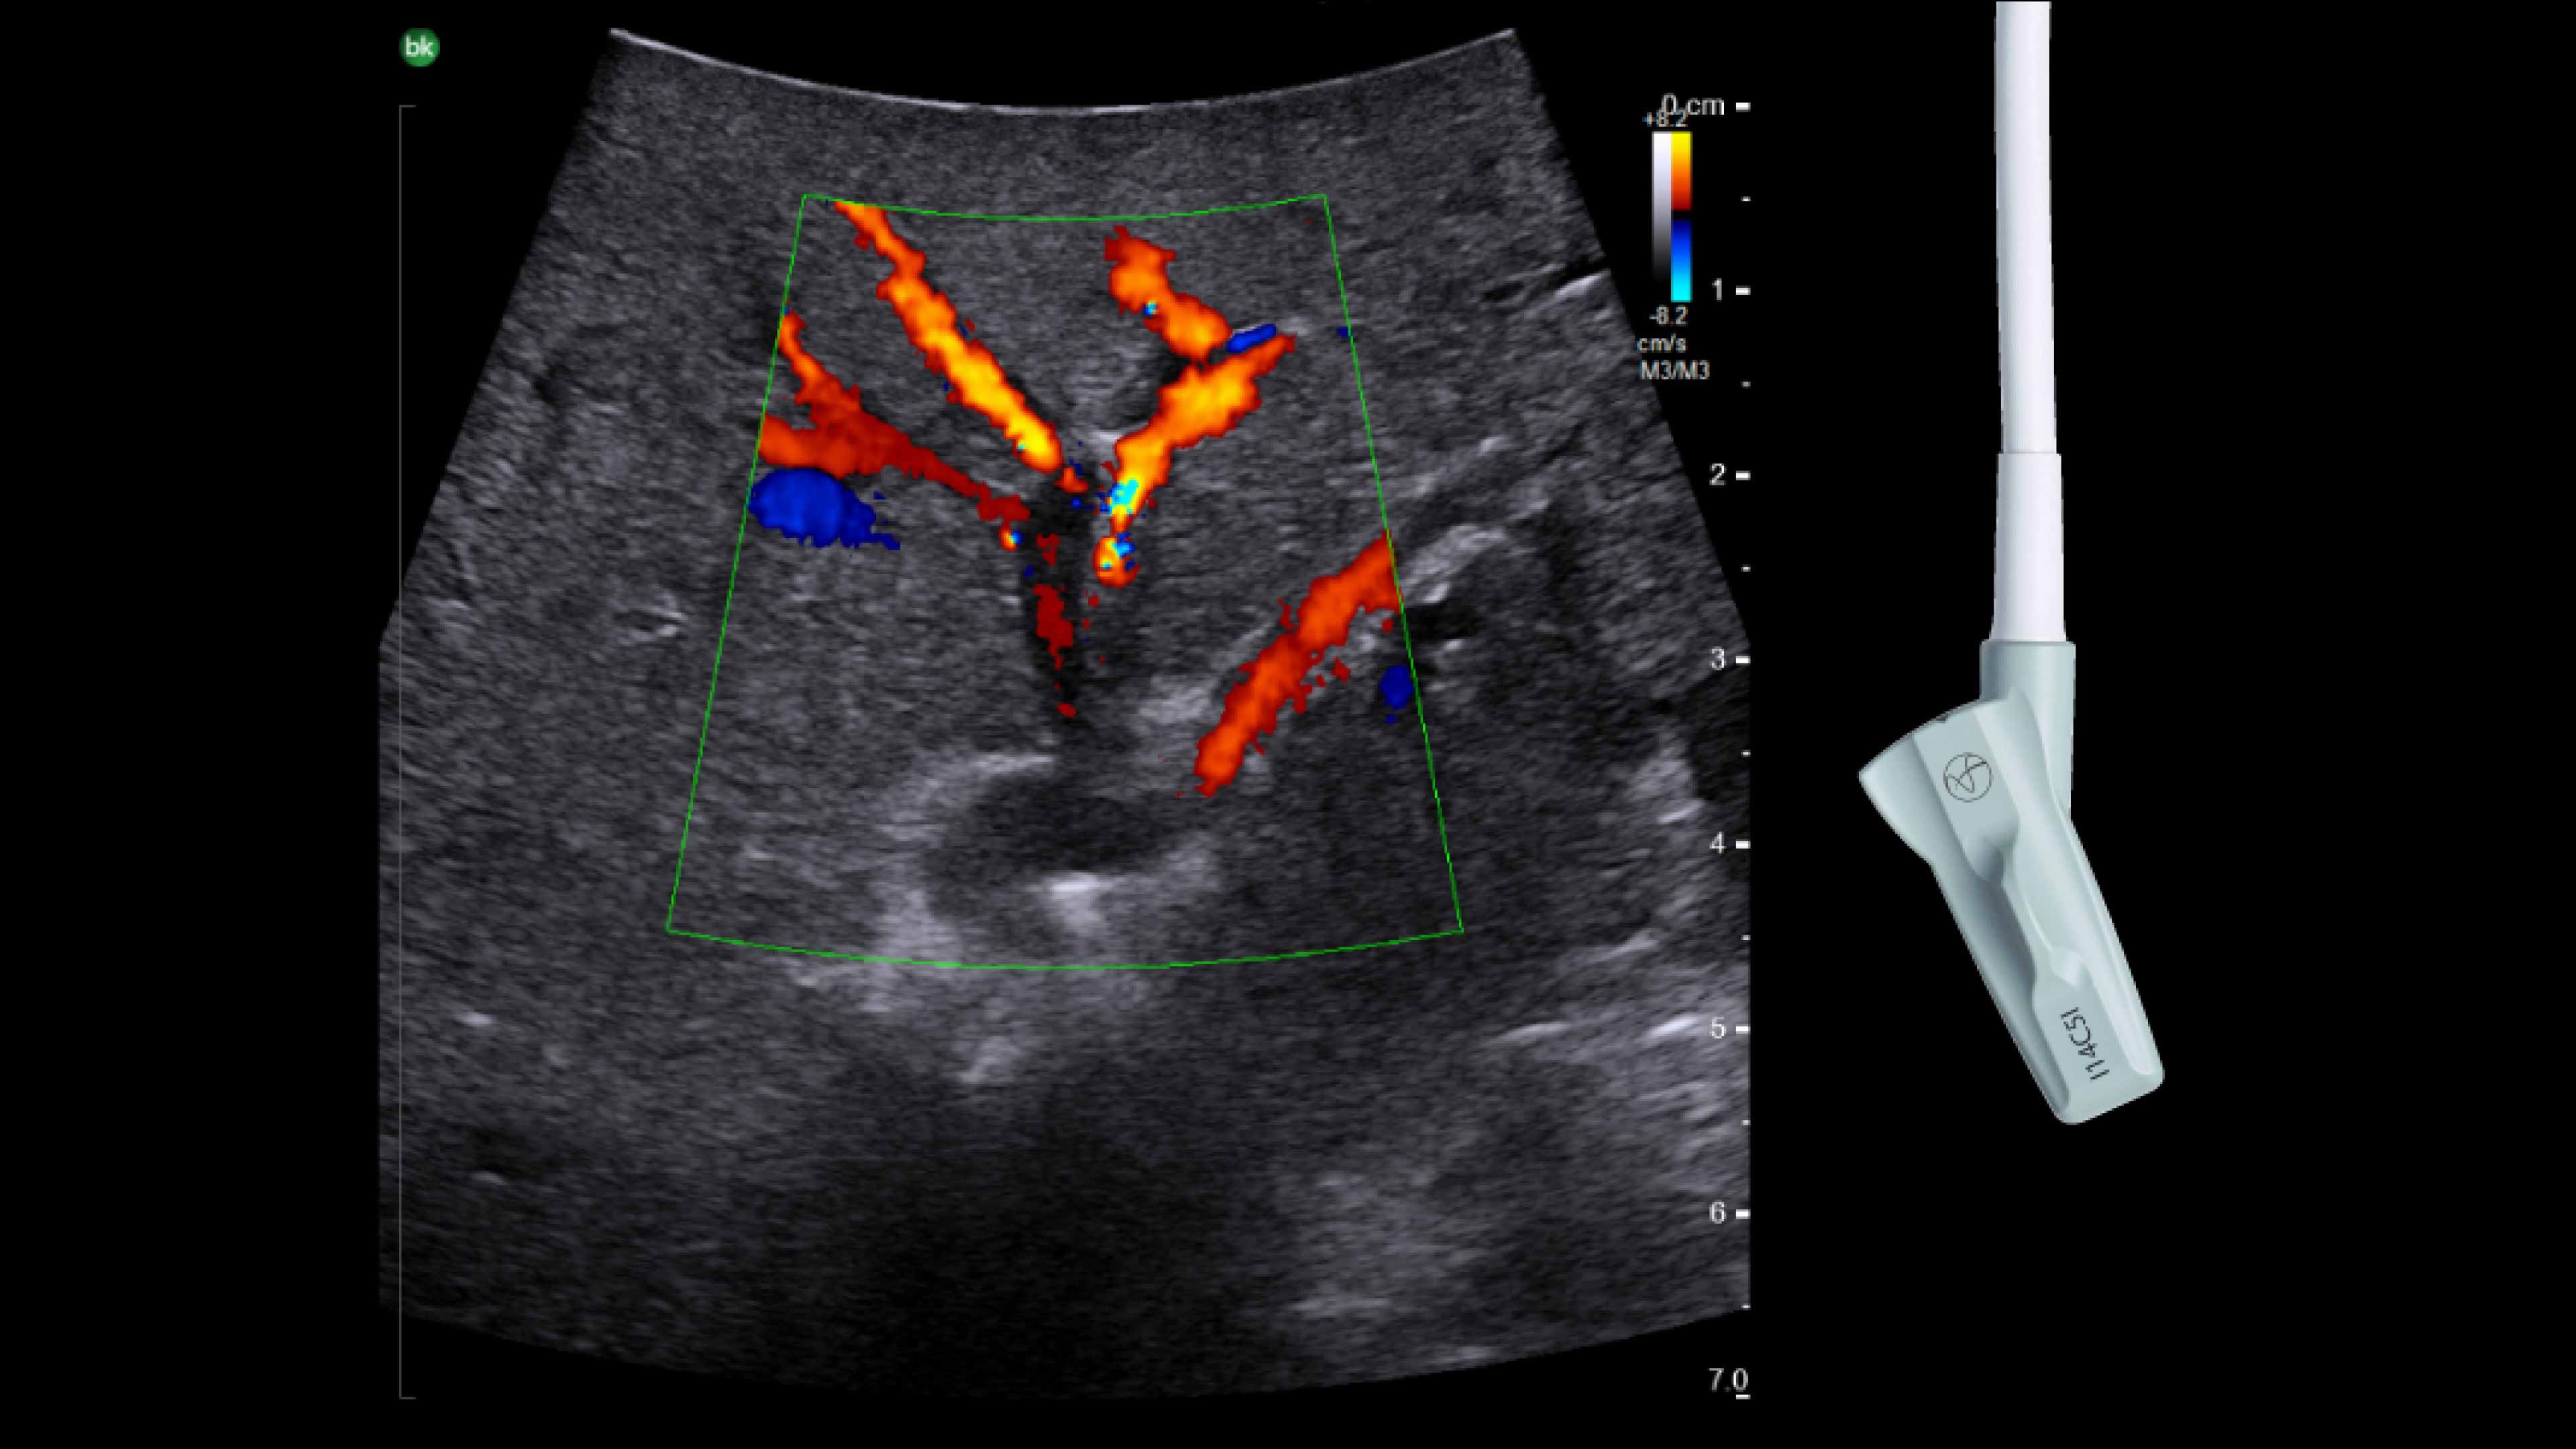

Active imaging supports liver and pancreas ablation procedures by helping you visualize lesions and blood vessels, identify healthy tissue vs. tumor, and guide and view needle placements.

Use intraoperative ultrasound to:

• Enable visualization of disease staging at the time of surgery with excellent image quality.

• Guide and view needle placements in real-time.

• Verify your planned results by assessing pre- and post-ablation images together.